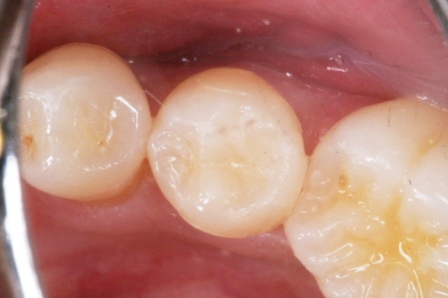

虫歯は金属の錆や腐食と同じ1.42 2025.11.10

虫歯は金属の錆や腐食と同じ1.41 2025.06.05